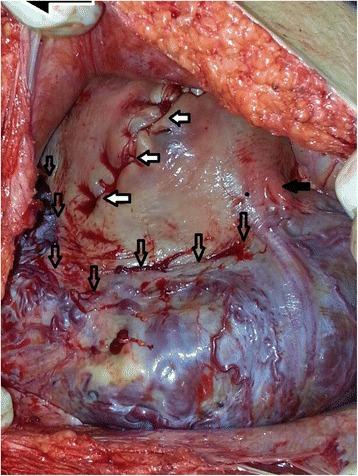

A patient with dichorionic twin pregnancy underwent to cesarean section (CS) due to preliminary diagnosis of placenta percreta at her 35(th) week of pregnancy. Both of the placentas were left in situ. The patient admitted with signs of infection. Emergency total abdominal hysterectomy was performed 7 weeks after CS. In the course of hysterectomy, 3 units of erythrocyte suspension and 2 units of fresh frozen plasma were transferred, whereas none was required during CS.

一名双绒毛膜双胎妊娠患者在妊娠35周时因初步诊断为穿透性胎盘而接受剖宫产(CS)。两个胎盘均留在原位。患者因感染迹象入院。剖宫产术后7周进行了急诊全腹子宫切除术。在子宫切除术中,输注了3单位红细胞悬液和2单位新鲜冰冻血浆,而剖宫产术中未输血。